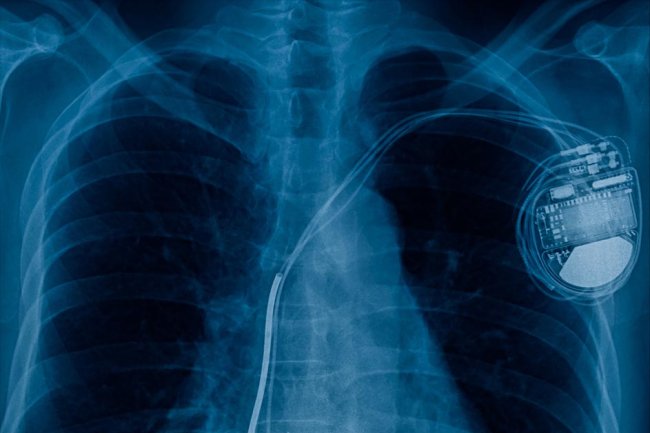

Leidraad CIED implantatie

Het op een veilige en effectieve wijze implanteren van een CIED (pacemaker, ICD, ILR).